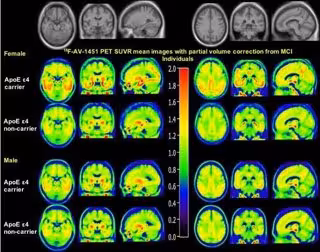

Archivo - Imagen de PET de cómo el sexo modula el efecto de ApoE e4

Archivo - Imagen de PET de cómo el sexo modula el efecto de ApoE e4 - PARANJPE M, LIU M, PARANJPE I, ET AL. - Archivo